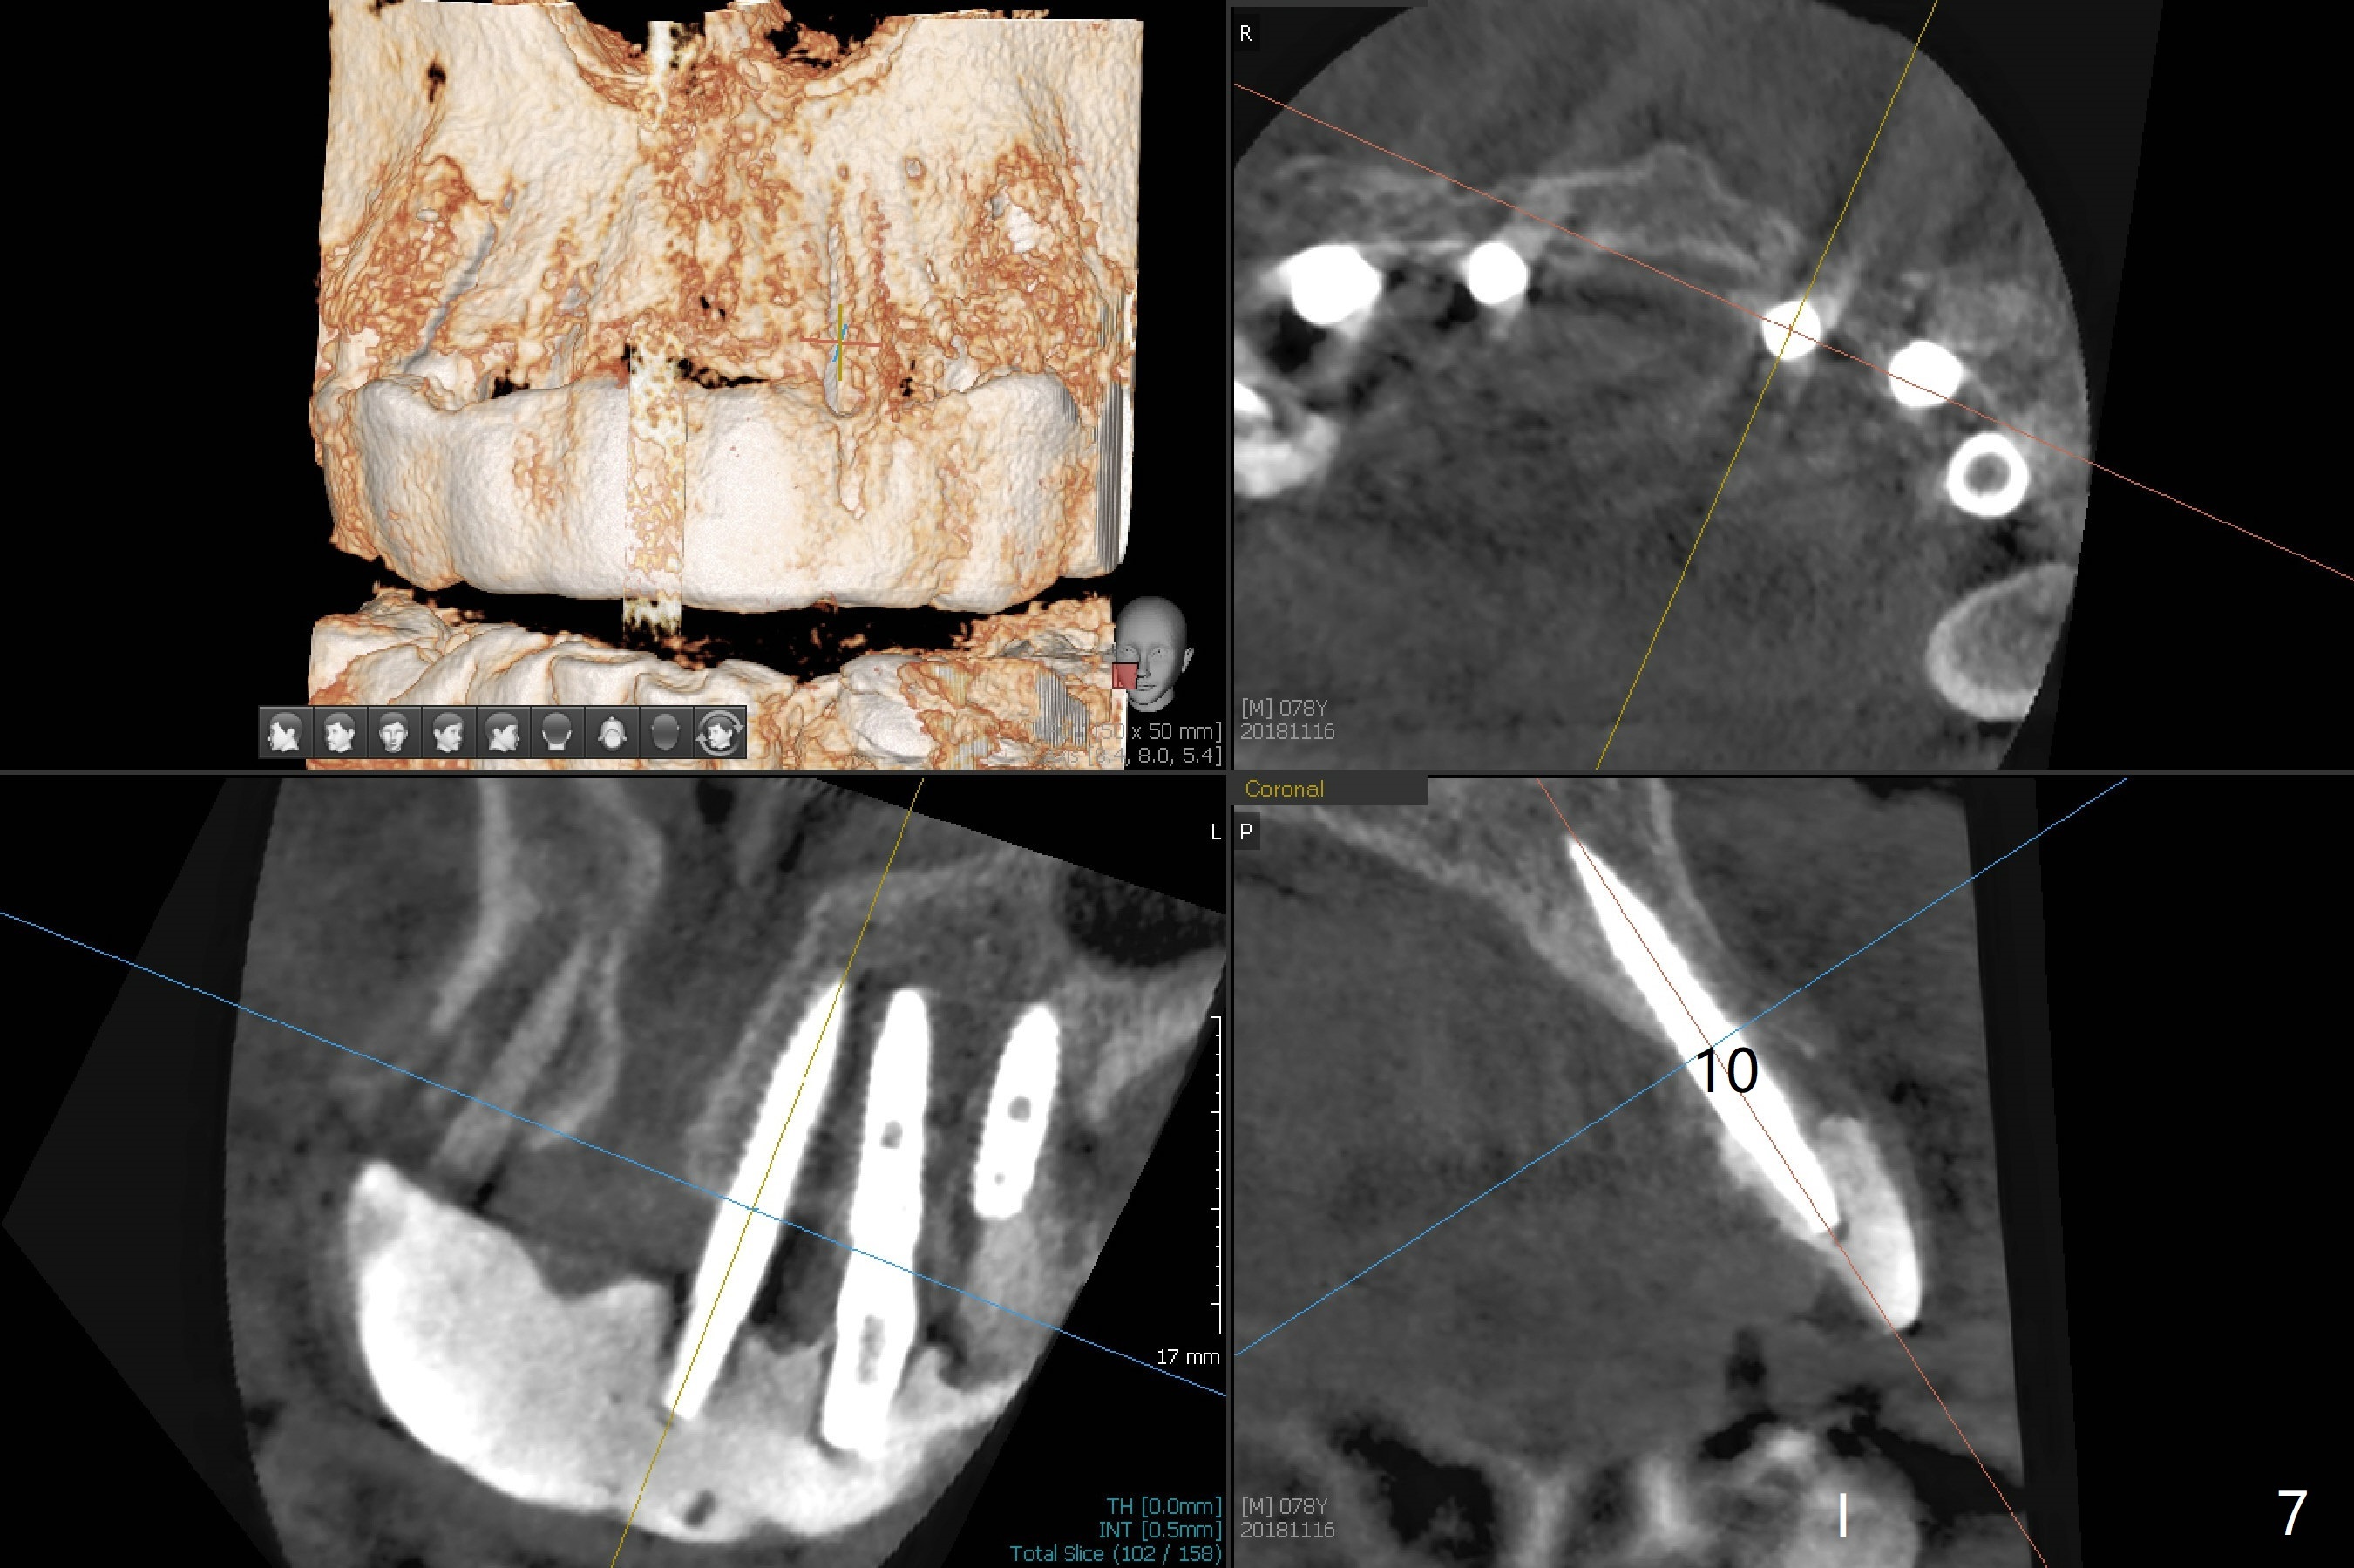

It is smooth and quick to finish osteotomy with guide at #6,7,10-12, but when 3 mm 1-piece implants are placed free hand at #7 and 10 (Fig.1,2), the gingival parts of the abutments contact the incisal edges of the lower incisors (anterior deep bite) in spite of effort to change the trajectory by repeated back and forth placement after use of Lindamann bur buccally. Following an immediate provisional (Fig.3,4), the occlusal surface of the posterior teeth are raised to eliminate anterior restoration interference. Immediate postop CBCT shows that the implants at #7 and 10 could be placed more buccally (Fig.6,7, as compared to the normal position at #6,11,12 (Fig.5,8,9)). Fig.10 was taken 2 days preop, while Fig.11-13 postop. Can we change 1-piece implants (3mm) at #7 and 10 to 2-piece one (3.5) and use angled or cementation abutments for easy restoration (Fig.14-16)?